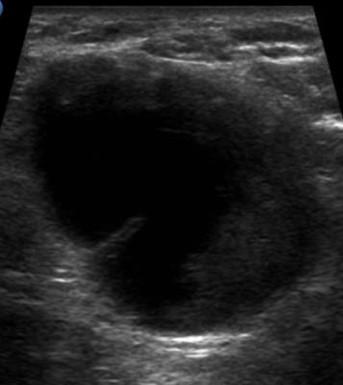

Ung thư vú - Ảnh 4

Ung thư vú

» Thông tin: Nữ giới – 57 tuổi.

» Lâm sàng: Khối tuyến vú.